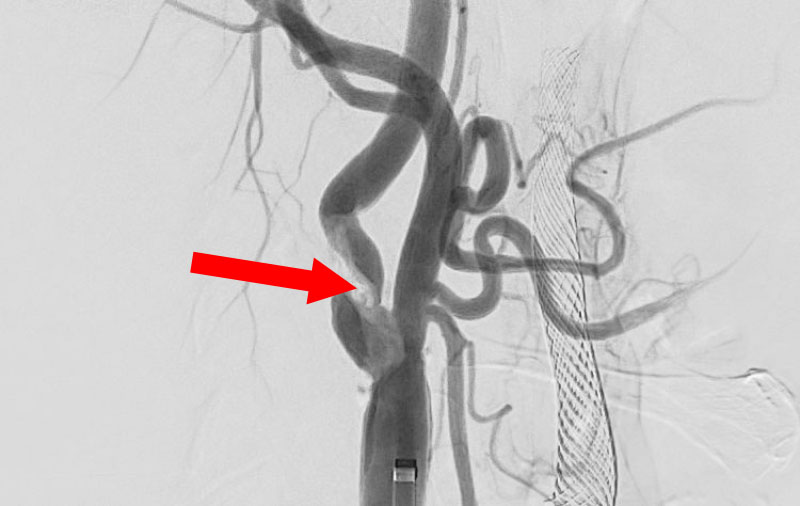

'25年10月

左総頚動脈狭窄症

30代

院内外来

No.1590 手術前

No.1590 手術中

No.1590 手術後